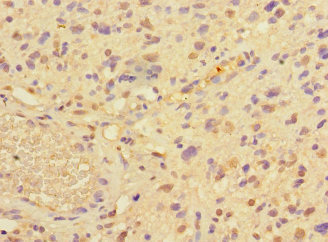

Immunohistochemistry of paraffin-embedded human glioma using CSB-PA018733LA01HU at dilution of 1:100